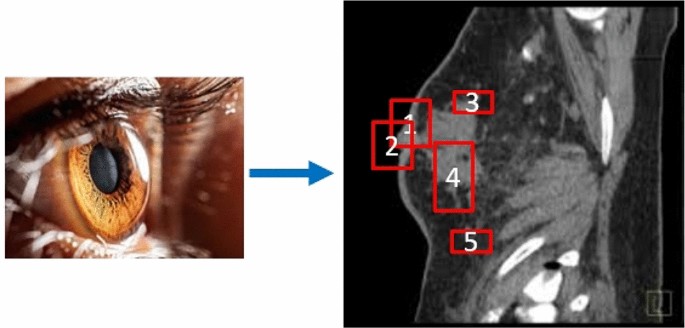

The workflow for the proposed rank-based framework to capture the gaze shift sequence (GSS) from large-scale breast cancer images. The process begins by extracting potential abnormalities using BING to generate object patches. A weakly-supervised ranking algorithm selects prominent patches, which are then linked to form the GSS. These are processed through a hierarchical aggregation network and classified using an SVM to identify different types of breast cancer.

To address these challenges, we introduce a rank-based framework designed to emulate the human gaze shift sequence (GSS), as shown in Fig. 1. This algorithm forms the foundation of a framework tailored to capture GSS from large-scale breast images. Our approach uses BING (Binarized Normalized Gradients)1 to extract potential abnormalities and generate object patches from each image. Given the large number of patches and computational constraints, analyzing each one individually is impractical. We propose a weakly-supervised ranking algorithm that identifies prominent patches by combining multiple subtle features. These selected patches are linked sequentially to form the GSS. A hierarchical aggregation network is then used to create a multi-layer hierarchical representation for each GSS. Using this representation, an SVM is trained to classify different types of breast cancer in the images.

Our newly devised algorithm, which employs a weakly-supervised ranking framework, reveals a compelling pattern: the highest-ranked object patches, notable for their high quality, exhibit both visual and semantic prominence that naturally captures the gaze. This phenomenon is illustrated in Fig. 2. Typically, the human gaze is drawn initially to the most conspicuous object patch before migrating to the next in order of salience. Leveraging this behavioral insight, we crafted the Gaze Shift Sequence (GSS) to emulate the human process of sequentially engaging with multiple areas of interest in an image. In practical application, once the GSS is established and assuming it comprises multiple salient object patches, we first engineer a 128-dimensional feature vector calculated by standard CNN to describe each salient patch, which provides a representative descriptor of the individual patch’s attributes. Such 128-dimensional feature vector capture each salient patch’s color, texture, and spatial layout collaboratively. Herein, the Patch-CNN is actually an MLP fine-tuned using our million-scale breast cancer images. These descriptors are then combined to form a comprehensive (128A)-dimensional vector, encapsulating the essence of the full GSS with A object patches.

The figure illustrates the Gaze Shift Sequence (GSS) construction process, where top-ranking object patches are linked to reflect human gaze behavior. A 128-dimensional feature vector for each salient patch is generated using Patch-CNN, which is then combined to form a comprehensive vector representing the full GSS.